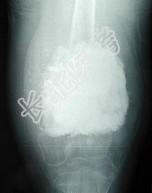

- 单项选择题女,10岁, 左大腿疼痛,夜间加重, 肿胀明显,请结合影像图像, 最可能的诊断为 ( )

A、骨化性肌炎

B、成骨性骨转移

C、化脓性骨髓炎

D、骨肉瘤

E、以上都不正确